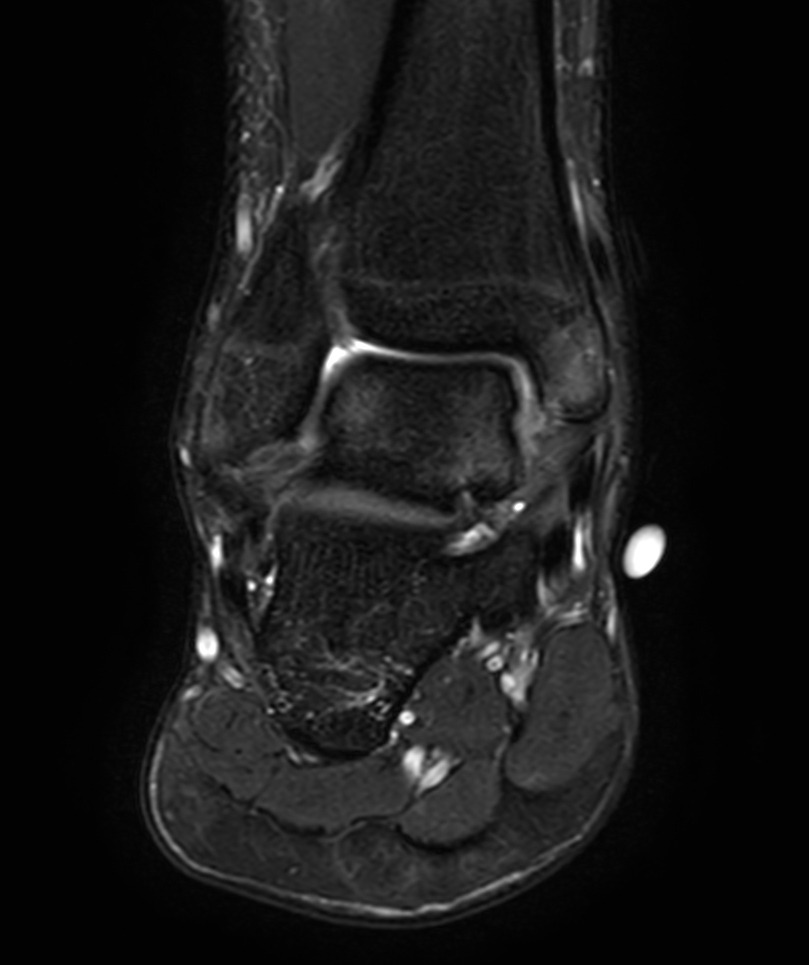

High resolution Ankle imaging in short scan times

Spital Uster, Switzerland

Coronal T2w TSE - mDIXON XD (In Phase)

Coronal T2w TSE - mDIXON XD (Water only)